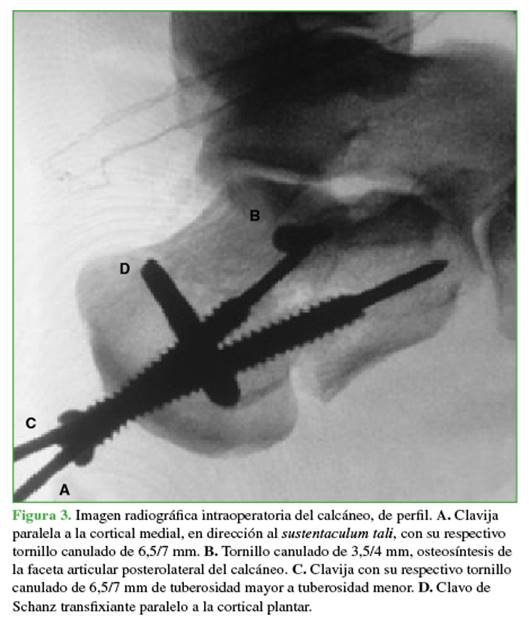

Se coloca un clavo de Schanz transfixiante en la tuberosidad mayor del calcáneo, de lateral a medial, marcando el punto de entrada en la proyección de perfil, proximal a la cortical plantar. Se orienta el clavo de Schanz perpendicular a la tuberosidad mayor y se evalúa el paralelismo de ese clavo de Schanz a la cortical plantar en la proyección axial (Figura 1A).

El primer ayudante procede a efectuar la tracción utilizando el clavo de Schanz transfixiante corrigiendo la deformidad. Se realiza una tracción axial y en varo/valgo para recuperar así la anatomía del calcáneo por ligamento-taxis. Luego, se coloca una primera clavija guía (para tornillo de posición de 6,5/7 mm) paralela a la cortical medial para solidarizar la tuberosidad mayor al fragmento sustentacular, reparo anatómico generalmente no desplazado y estable (Figura 1B).

A continuación, se procede con el AbST y la reducción por la visualización directa de la FAPLc (Figura 2). Fijación de la FAPLc con una o dos clavijas. Se colocan de lateral y posterior a anterior y medial, dirigidas al sustentaculum tali. Posteriormente se sustituyen por tornillos canulados en compresión de 3,5/4 mm (Figura 1C). Por último, se coloca la segunda clavija guía (línea C) que será sustituida por un tornillo canulado, de rosca completa de 6,5/7 mm. Esta corre paralela a la cortical lateral y solidariza la tuberosidad mayor con la menor (Figuras 1D y 3).

La cantidad y orientación de los tornillos de 6,5/7 mm dependerá de los trazos de fractura. El objetivo de estos es solidarizar la tuberosidad mayor con el cuerpo del calcáneo y con la tuberosidad menor, generando además un “andamiaje” que le brinde estabilidad a la carilla articular posterolateral (Figuras 4-6).